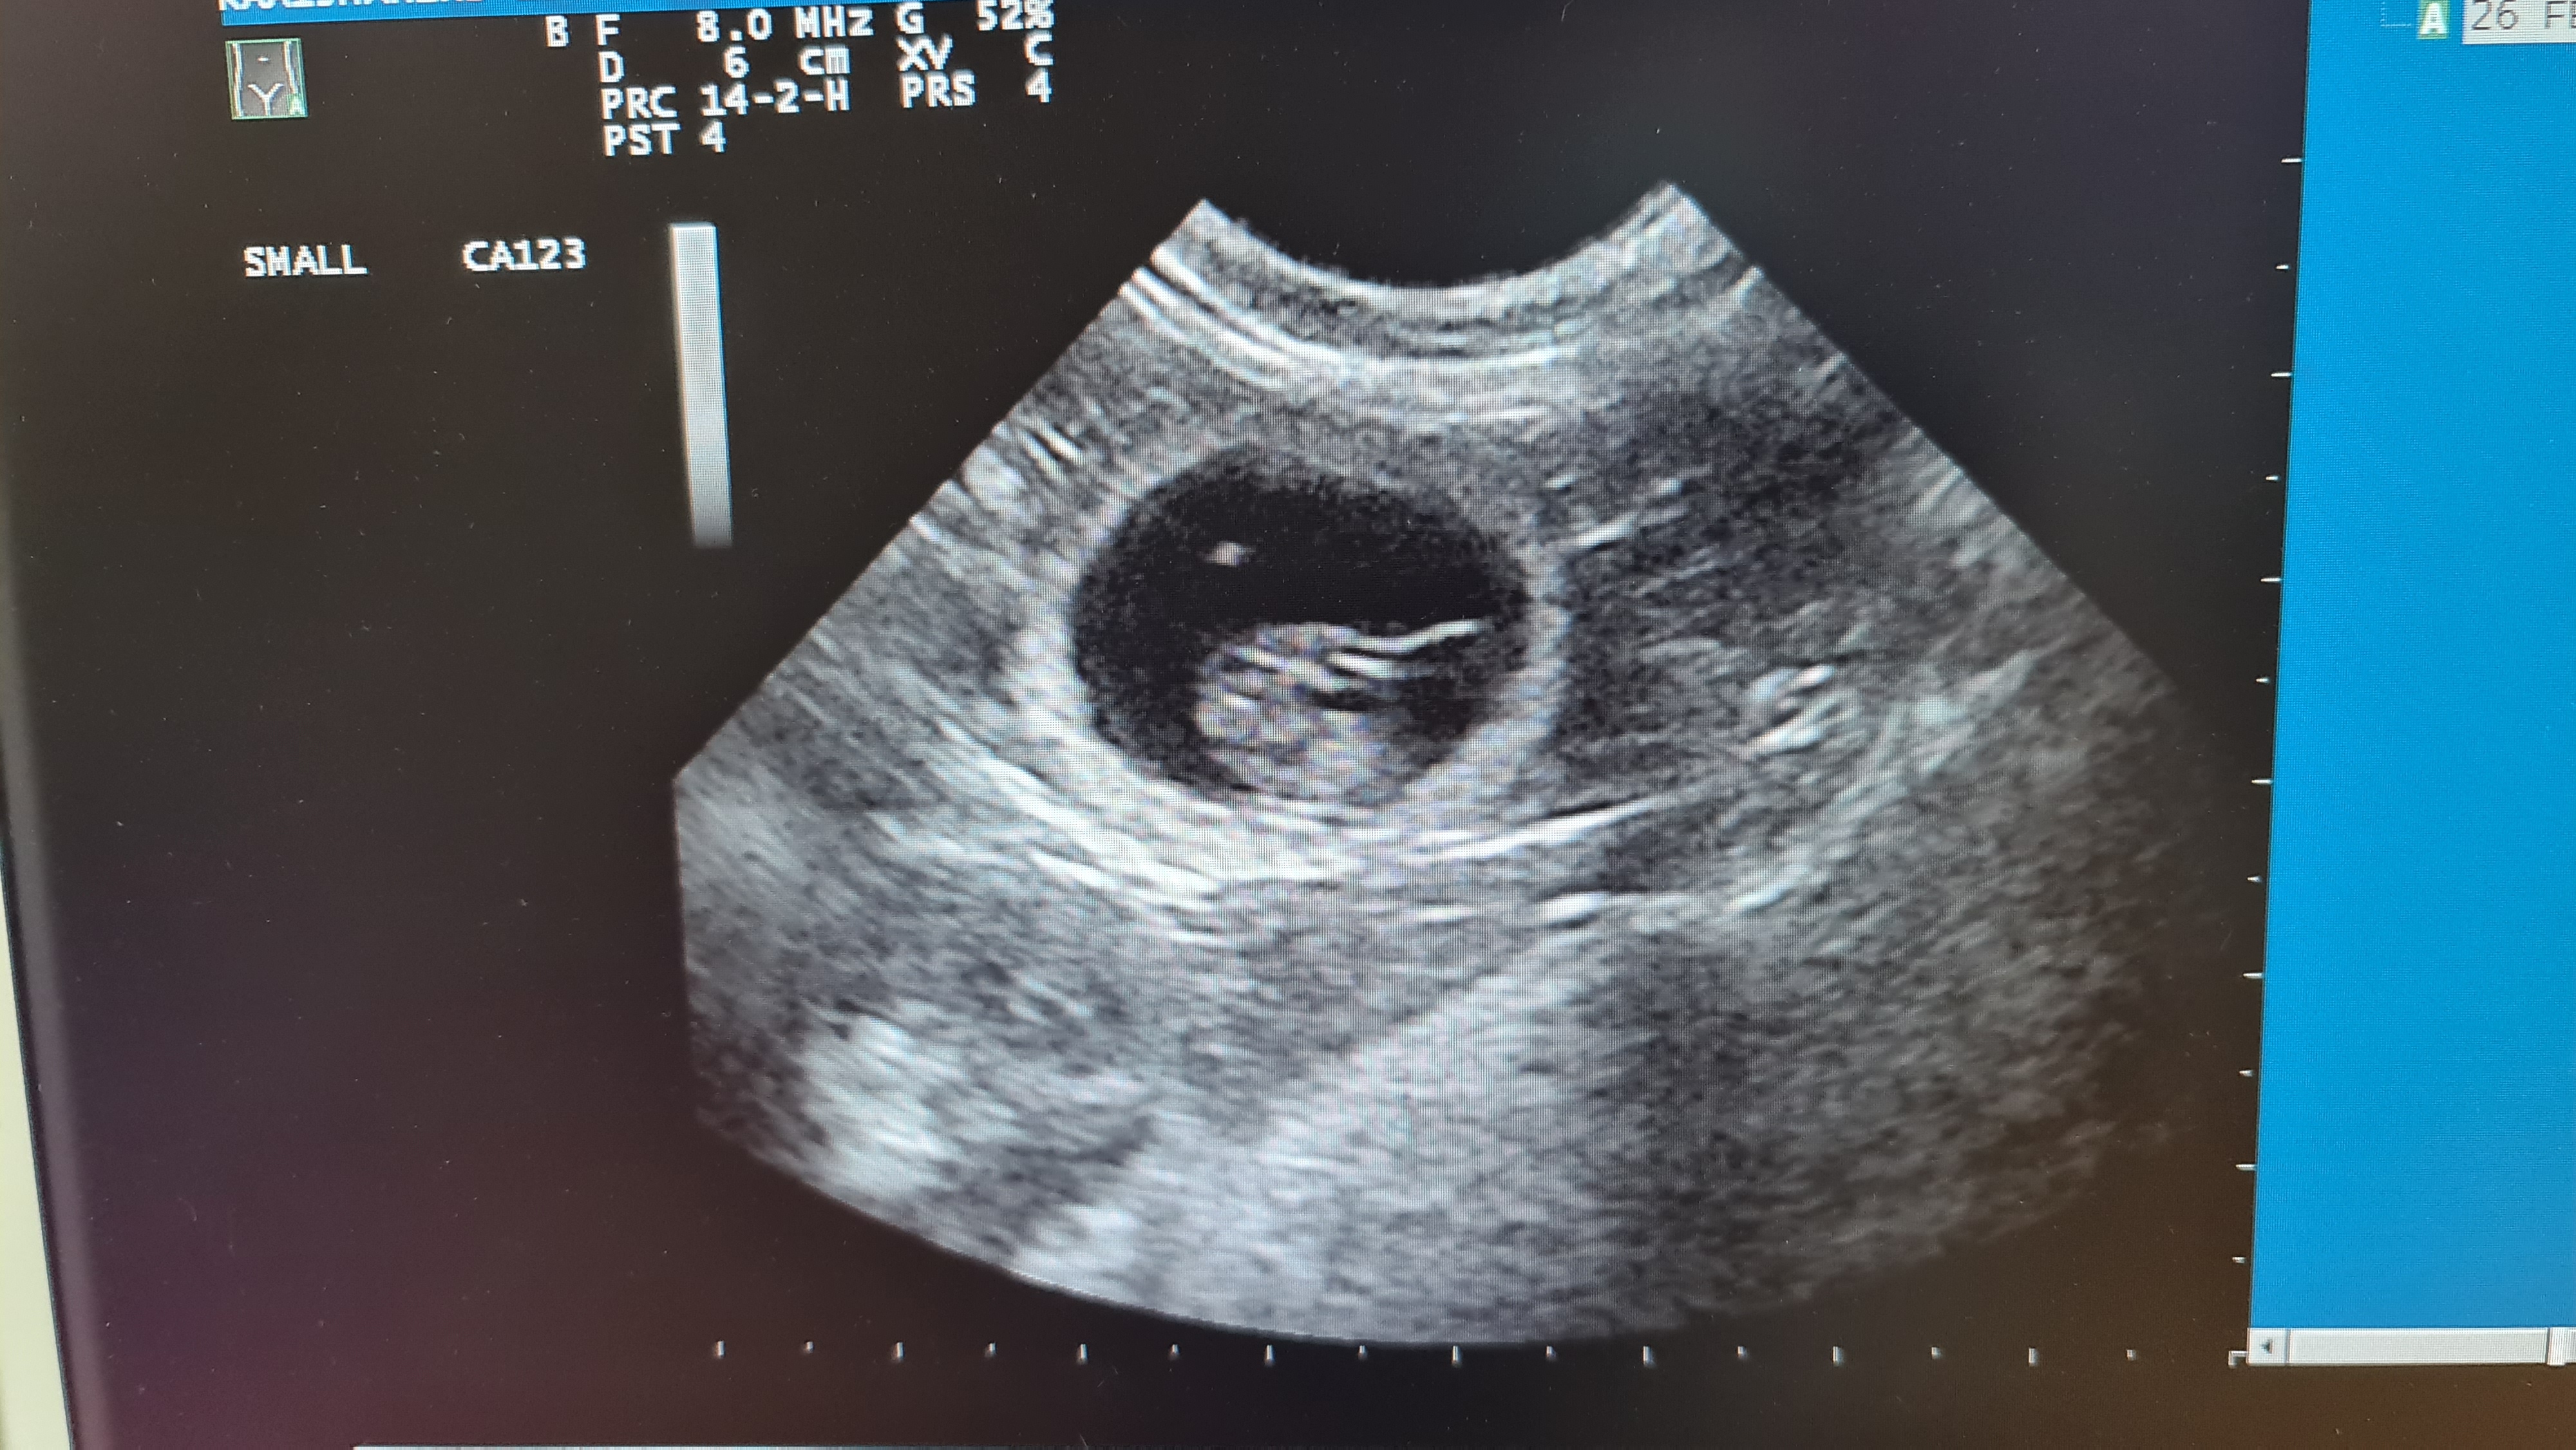

GOED NIEUWS Eindelijk kunnen wij ook vertellen dat we een zwangere dame in huis hebben. Mili heeft een succesvolle date gehad met Bikimi’s Salvador Dali. Een echo heeft uitgewezen dat er maar één kitten zichtbaar is. Stiekem hopen we natuurlijk dat er nog een kitten verstopt zit, maar daar gaan we niet van uit. Als alles goed verloopt, mogen we dit kleine wondertje begin april verwelkomen.